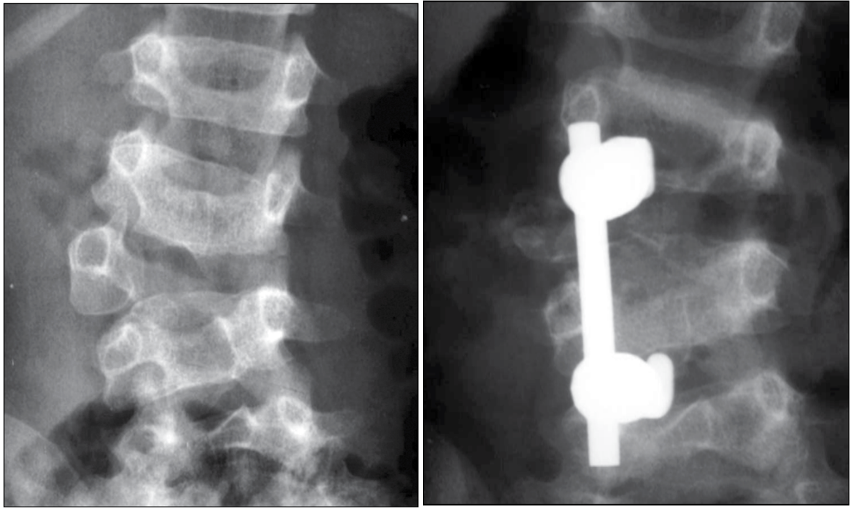

Ressecção de vértebra malformada (hemivértebra)

Quando a deformidade está concentrada em uma vértebra específica malformada, pode ser indicada a retirada cirúrgica dessa vértebra (hemivértebra), seguida de uma correção localizada com fusão curta.

Essa abordagem busca tratar a causa da deformidade, permitindo boa correção da curva e preservando o máximo possível da mobilidade da coluna nos segmentos não acometidos.

Ao se considerar estudos cirúrgicos, obeserva-se que a ressecção posterior de hemivértebra com fusão curta é eficaz para correção de deformidades focais, com bons resultados em seguimentos de médio e longo prazo. Em contraste, deformidades congênitas mais extensas, envolvendo múltiplas anomalias vertebrais, tendem a exigir estratégias mais complexas e apresentam maior risco de progressão residual ou falhas mecânicas.